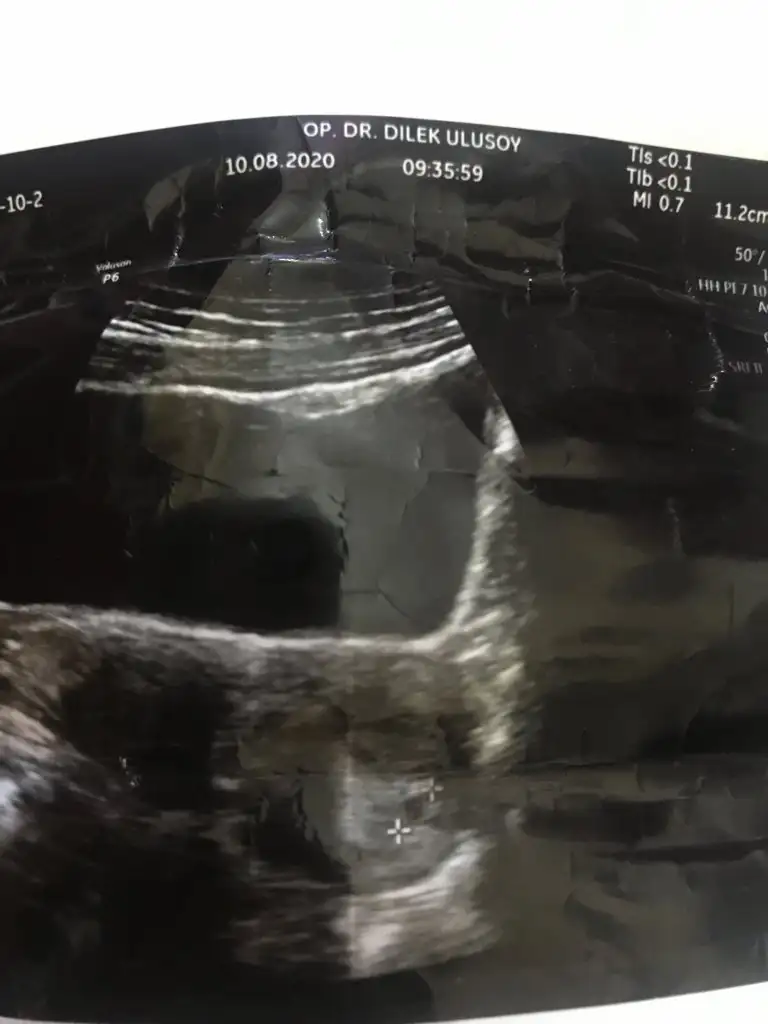

Pazartesi günü kontrolüm vardı canım keseyi gördük çok şükür önümüzdeki çarşamba doktorum kalp atışı için çağırdı bakalım onun heyecanı var şimdi ☺🌸

Ne kadarlık olduğunu söylemedi ama kesesini oluşturuyor dedi kesemiz daha ufacık ☺️

Kızlar bugün kontrole gittim çok heyecanlandım. Üstten sadece kese gorunuyordu belli belirsiz, alttan bakabilirim istersen dedi bende kabul ettim. Alttan çok net kese ve bebiş göründü hatta kalp atışı bile belli oluyordu gösterdi bak pıt pıt hareket eden yer bebeğinin kalbi dedi. Çok şükür hersey yolunda. Bir ay sonra gel dedi. Testlerinide aile hekiminden ücretsiz yaptırabilirsin masrafa gerek yok dedi. Doktorumu çok seviyorum,

Ay cok sevindim ya iyiki alttan baktırmıssın 😊 benim kese net gözüktü üstten büyüktü demekki alttan baksa benimde varsa herşey cıkıcaktı Bana pazartesi 5 haftalık dedi seninle yakın sanırım